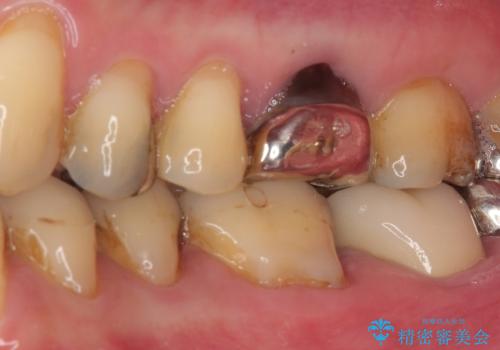

- 奥歯で食事がとれないくらいに痛むとのことで来院された患者です。

診察の結果、既に根管治療をされている第二大臼歯の根尖部に大きな病変があり、それが痛みの原因であるため、根管治療が必要と判断されました。

速やかに根管治療を行い、痛みの消退を確認の後、オールセラミッククラウンにて補綴治療を行うこととしました。